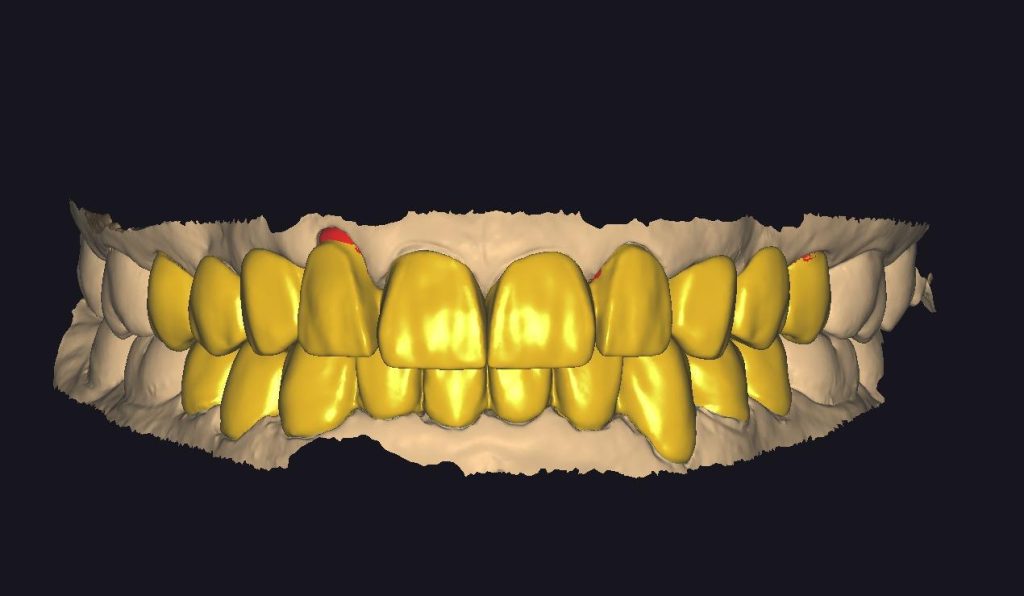

ZIRKONYUM

IMPLANT USTU ZIRKONYUM